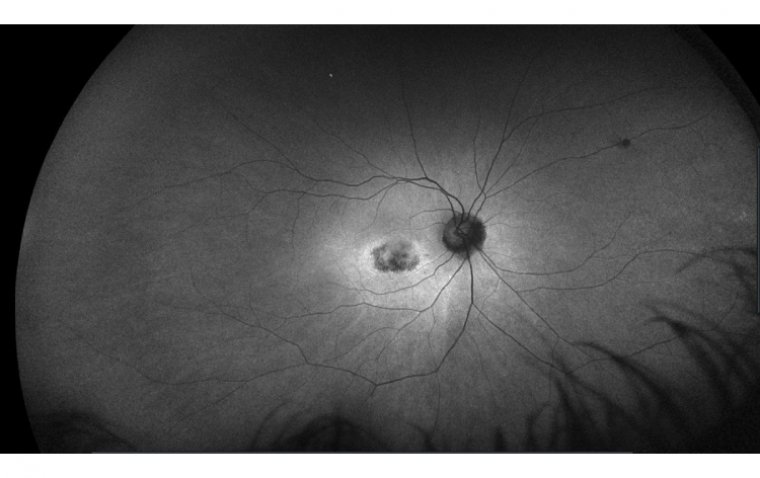

Токсическое поражение сетчатки при терапии Plaquenil: обзор рисков и стратегий предотвращения

Токсическое поражение сетчатки Plaquenil — редкое, но серьезное осложнение терапии гидроксихлорохином при аутоиммунных заболеваниях. Риск зависит от дозы и длительности приема. Раннее выявление с помощью регулярных осмотров глаз позволяет предотвратить …